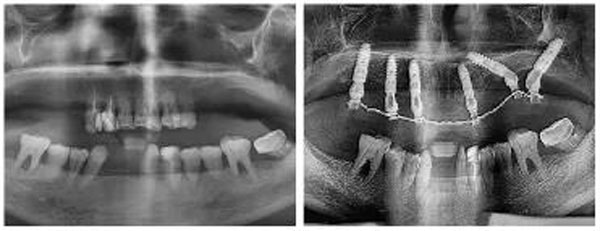

鄧女士種牙前全景片

多顆牙缺失+牙周病

讓她嘴角干癟,前牙外凸,嚴重影響面型

鄧女士種牙前后全景片對比